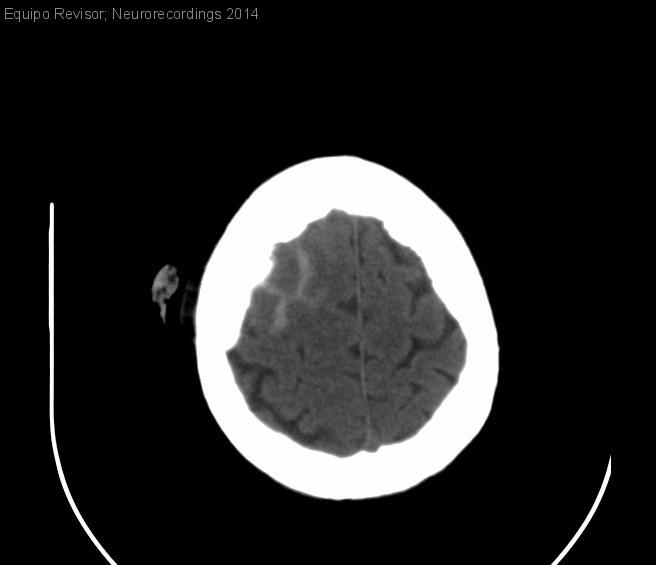

Hemorragia subaracnoidea tras TCE

Mujer | 71 años

Diagnóstico final: Hemorragia Subaracnoidea. TCE

Neurología: Patología cerebrovascular

Etiología: Ictus | Trauma